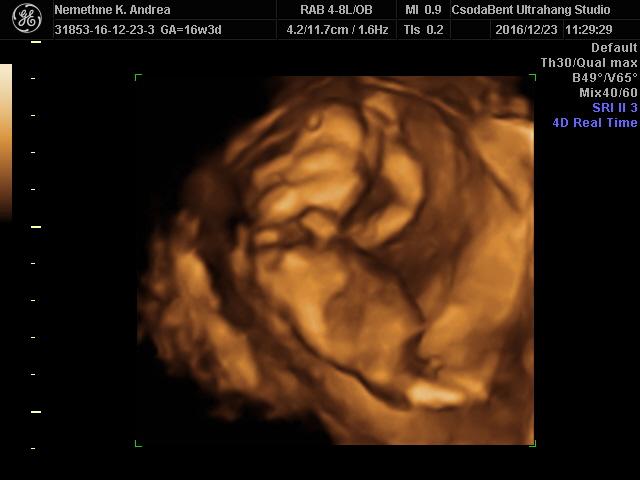

Mi pénteken megyünk a 4dre, és utána január végén lesz az 18.heti ultrahang, meg egy vér és vizelet.

De utána szép képeket és videót kaptunk róla, nagyon úgy néz ki hogy kisfiú!

Lilypie First Birthday tickers